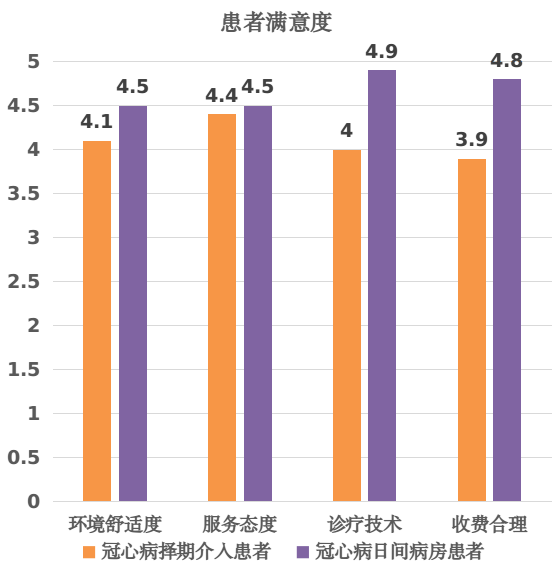

健康河源,共建共享。群众满意,是医疗卫生服务工作的出发点和落脚点,2022年度全省公立医院满意度调查结果显示,河源市公立医院门诊患者满意度得分87.88分,排名第4名;住院患者满意度得分90.09分,排名第12名。

“冠心病日间病房新模式”—同日完成冠心病介入诊疗及出入院,缩短患者就医时间,改善患者就医体验

——广东省人民医院河源医院

(一)优化冠心病介入诊治流程,缩短患者就医时间,保证医疗质量,建立冠心病介入治疗“日间病房”诊治新模式

广东省人民医院河源医院(河源市人民医院)积极响应国家号召,于2021年9月首次开展冠心病介入手术“日间病房”的创新模式。冠心病介入“日间病房”模式是一种高效、快捷、安全的手术模式,是以患者为中心、提高患者就医体验、改善患者就医感受、缩短患者就医时间为核心的创新型流程。具体流程为:①病情相对稳定的冠心病患者,在门诊就诊期间经过疾病和病情的初步评估,完善简单的肝肾功能等血液化验检查和心肺基本的影像辅助检查;②门诊医师通过冠心病患者的临床表现和检查结果进行全面评估,认为其适合接受冠脉造影及冠脉介入手术治疗;③预约固定某一天上午入院后,完善术前准备后送介入室或导管室进行手术检查及(或)介入治疗,手术过程顺利安返病房,经观察评估病情较为平稳,于当天下午或傍晚办理出院,回家休息。总结其为:入院-手术-出院于当天完成。

经过优化,这种冠心病介入手术“日间病房”模式变革了传统医疗观念,充分整合联动不同部门,形成高效率和高质量的诊疗单元,为患者带来诸多便利。在医生的指导下,患者通过门诊预约,完成相关检查后,患者可以当天入院接受手术,术后患者恢复迅速,无需陪护,缩短了住院时间,降低了医疗费用。这种模式不仅提高了医疗效率和质量,还减轻了家庭及国家的负担,广受患者的好评。

四、冠心病介入手术“日间病房”亮点

1.很好的切合目前党和政府为人民服务,改善人民群众生命健康和就医体验的大政方针;

2.“以患者为中心”借助住院服务中心打通“一站式院前服务”,既是优化医疗服务流程的结果,也是未来进一步继续开创医疗新模式的前提;

3.兼顾医疗技术与医院服务;服务理念先进,优质高效、有温度,助力心血管专科发展及患者满意度提升,综合效果显著;

4.极大的降低了部分患者的经济负担、时间与精力的消耗,显著降低住院费用,减轻人民群众与政府的医疗负担。

五、案例总结

在上级部门和领导的指导和支持下,冠心病介入“日间病房”模式得以迅速推广。通过严格的质量控制体系,确保手术的安全和有效,也确保住院当天术前准备和术后观察的高质量,极大的缩短了部分冠心病患者的就医时间和经济负担。同时,这种模式也需要患者具有良好的自我管理能力,积极配合医护人员的指导,共同为手术的成功和术后康复努力。

总之,冠心病介入“日间病房”模式是一种创新、务实、高效的医疗模式,为患者带来了福音。冠心病介入“日间病房”模式具备诸多优点,它在医疗领域拥有广泛的应用前景。随着医疗技术的不断进步以及人们健康意识的提高,这种高效率、低成本的医疗模式必将会受到越来越多医生和患者的青睐。在未来的发展中,我们相信这种模式将会得到更广泛的应用和推广,从而为更多的患者带来福音。